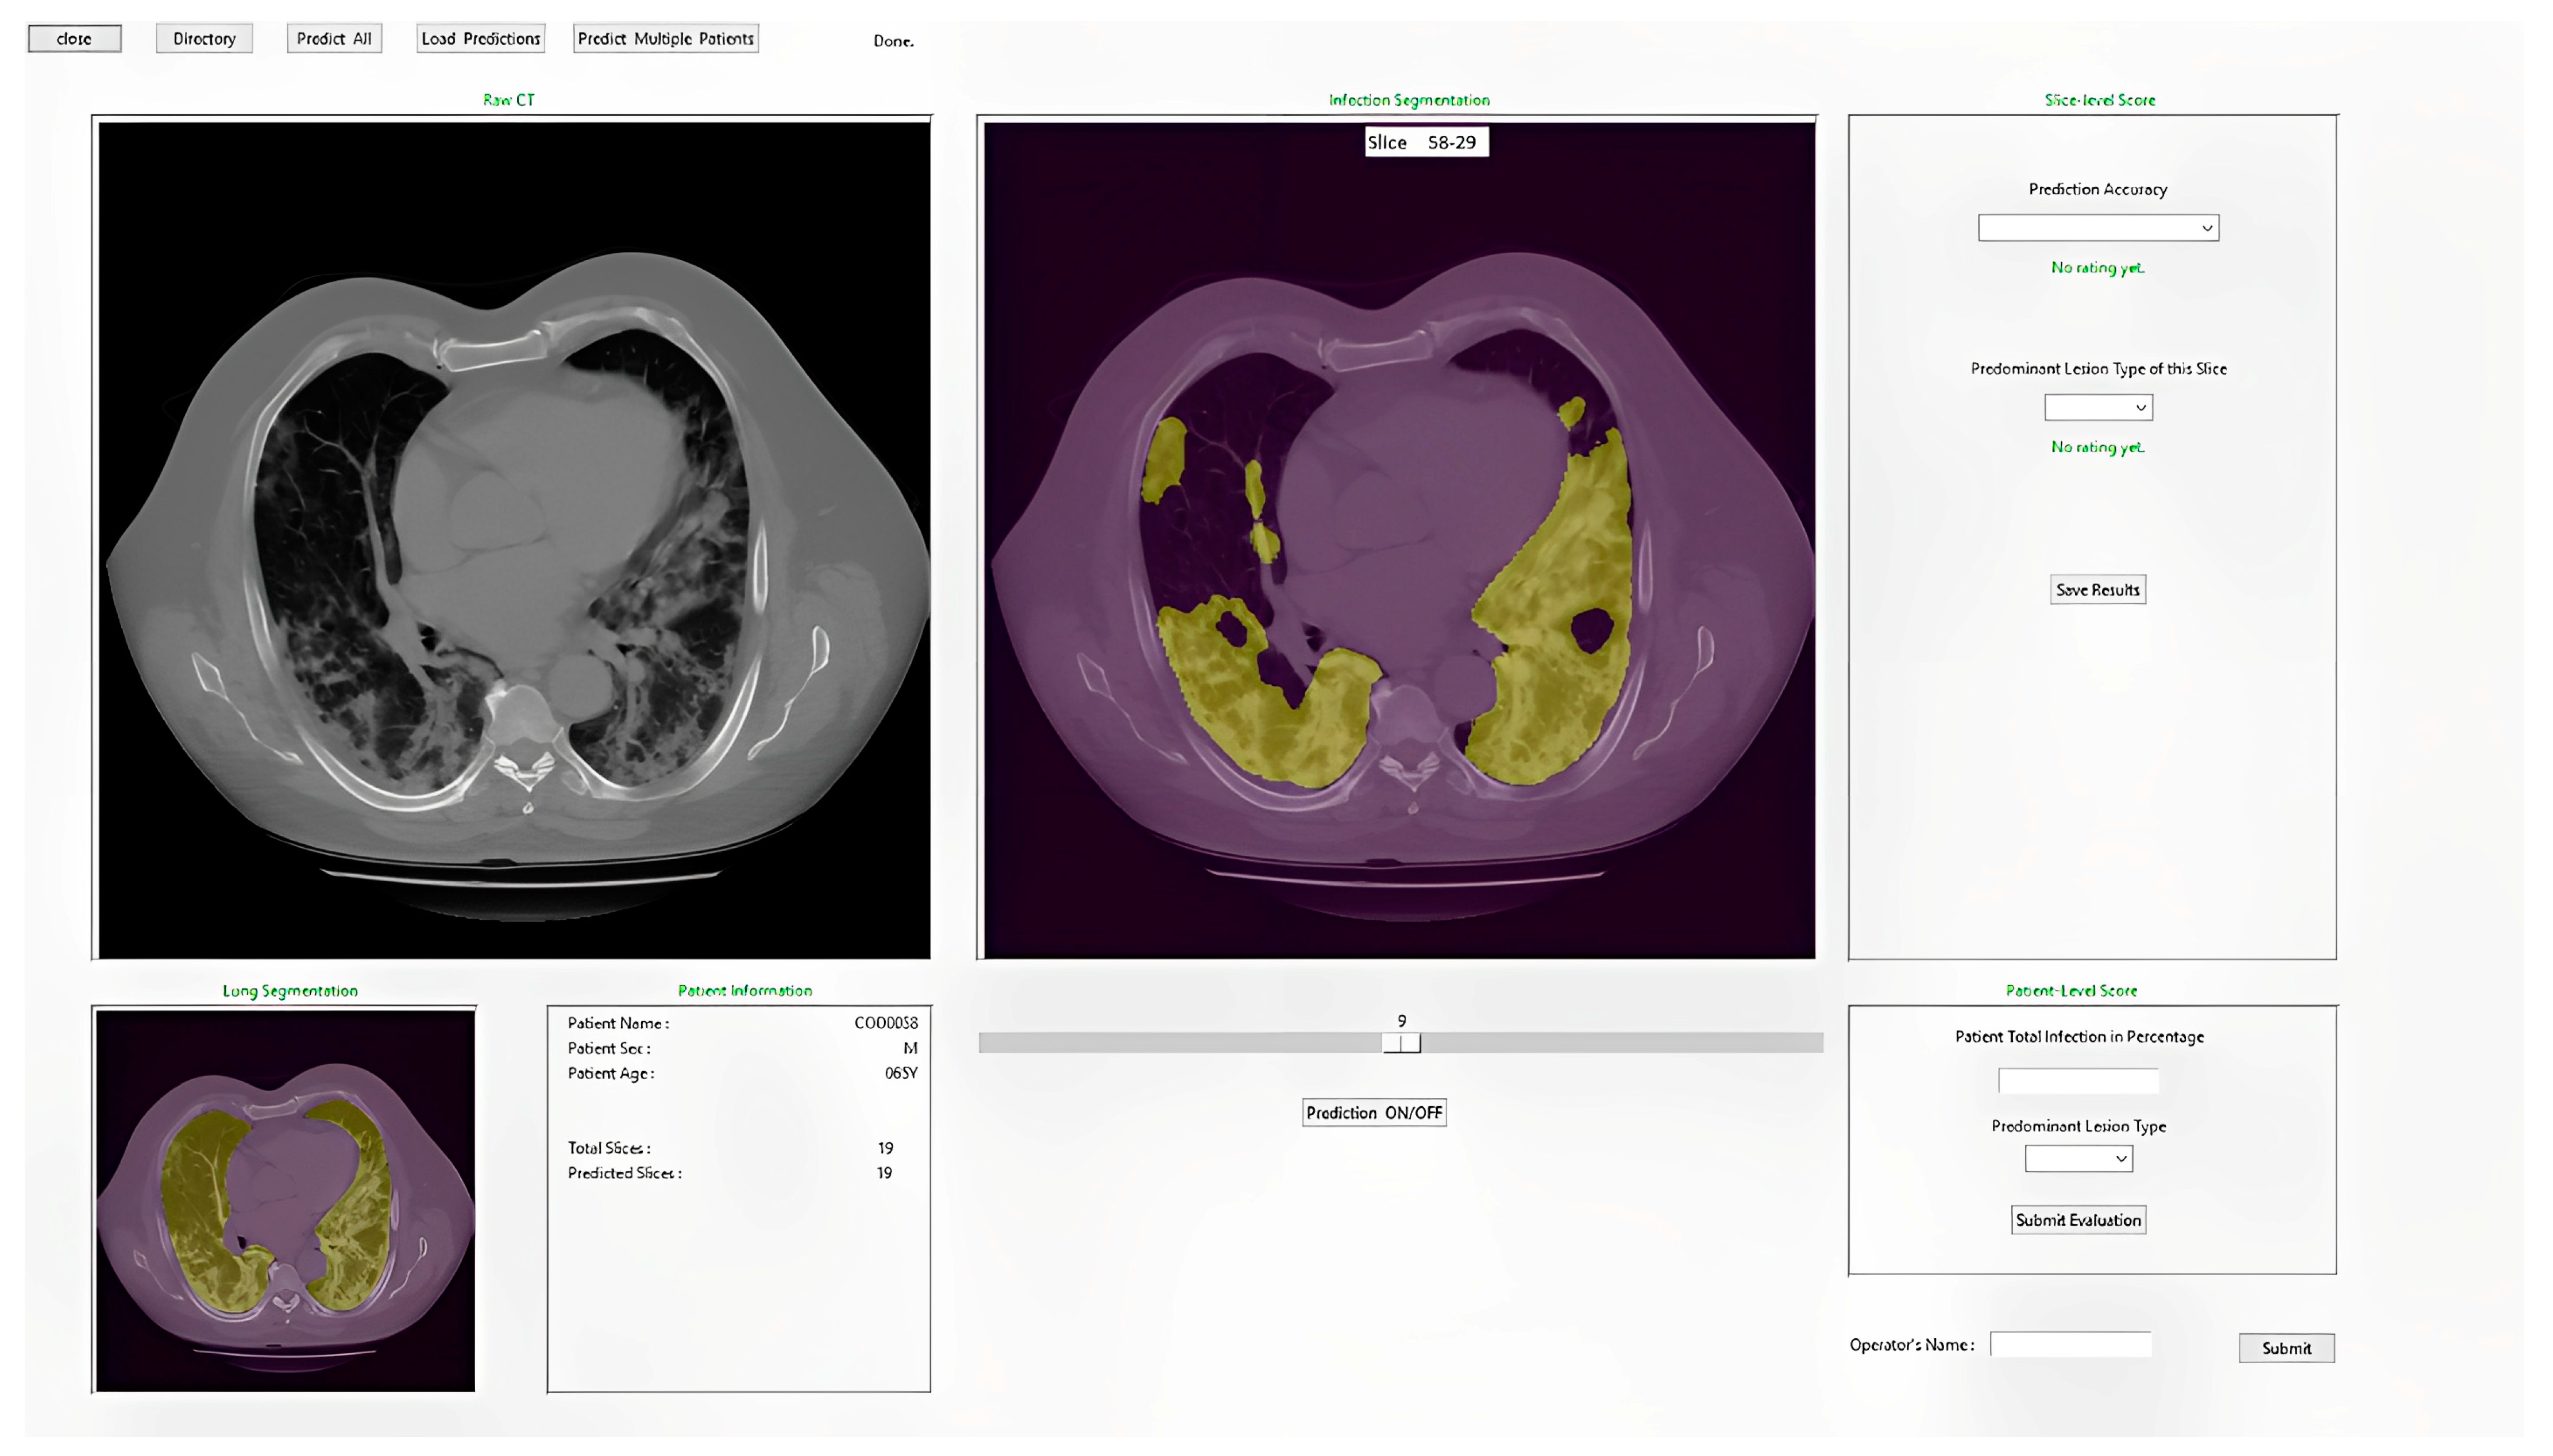

2.3.4. Integrated Model and GUI

3. Results

- (1)

- From Figure 10a, we observe that in 34% (27/80) of testing cases, the difference between the DL model generated diseased region segmentation and radiologist’s estimation is less than 5% (indicating the accuracy > 95%).

- (2)

- In 55% (44/80) of testing cases, the difference between the DL model generated diseased region segmentation and radiologist’s estimation is less than 10% (or accuracy > 90%).

- (3)

- In 90% (72/80) of testing cases, the difference between the DL model generated diseased region segmentation and radiologist’s estimation is less than 30% (or accuracy > 70%).

- (4)

- From Figure 10b, we observe that in 73% (58/80) of testing cases, radiologists rated a score of 3 or higher indicating an acceptable lung and disease-infection region segmentation results generated by the DL model.